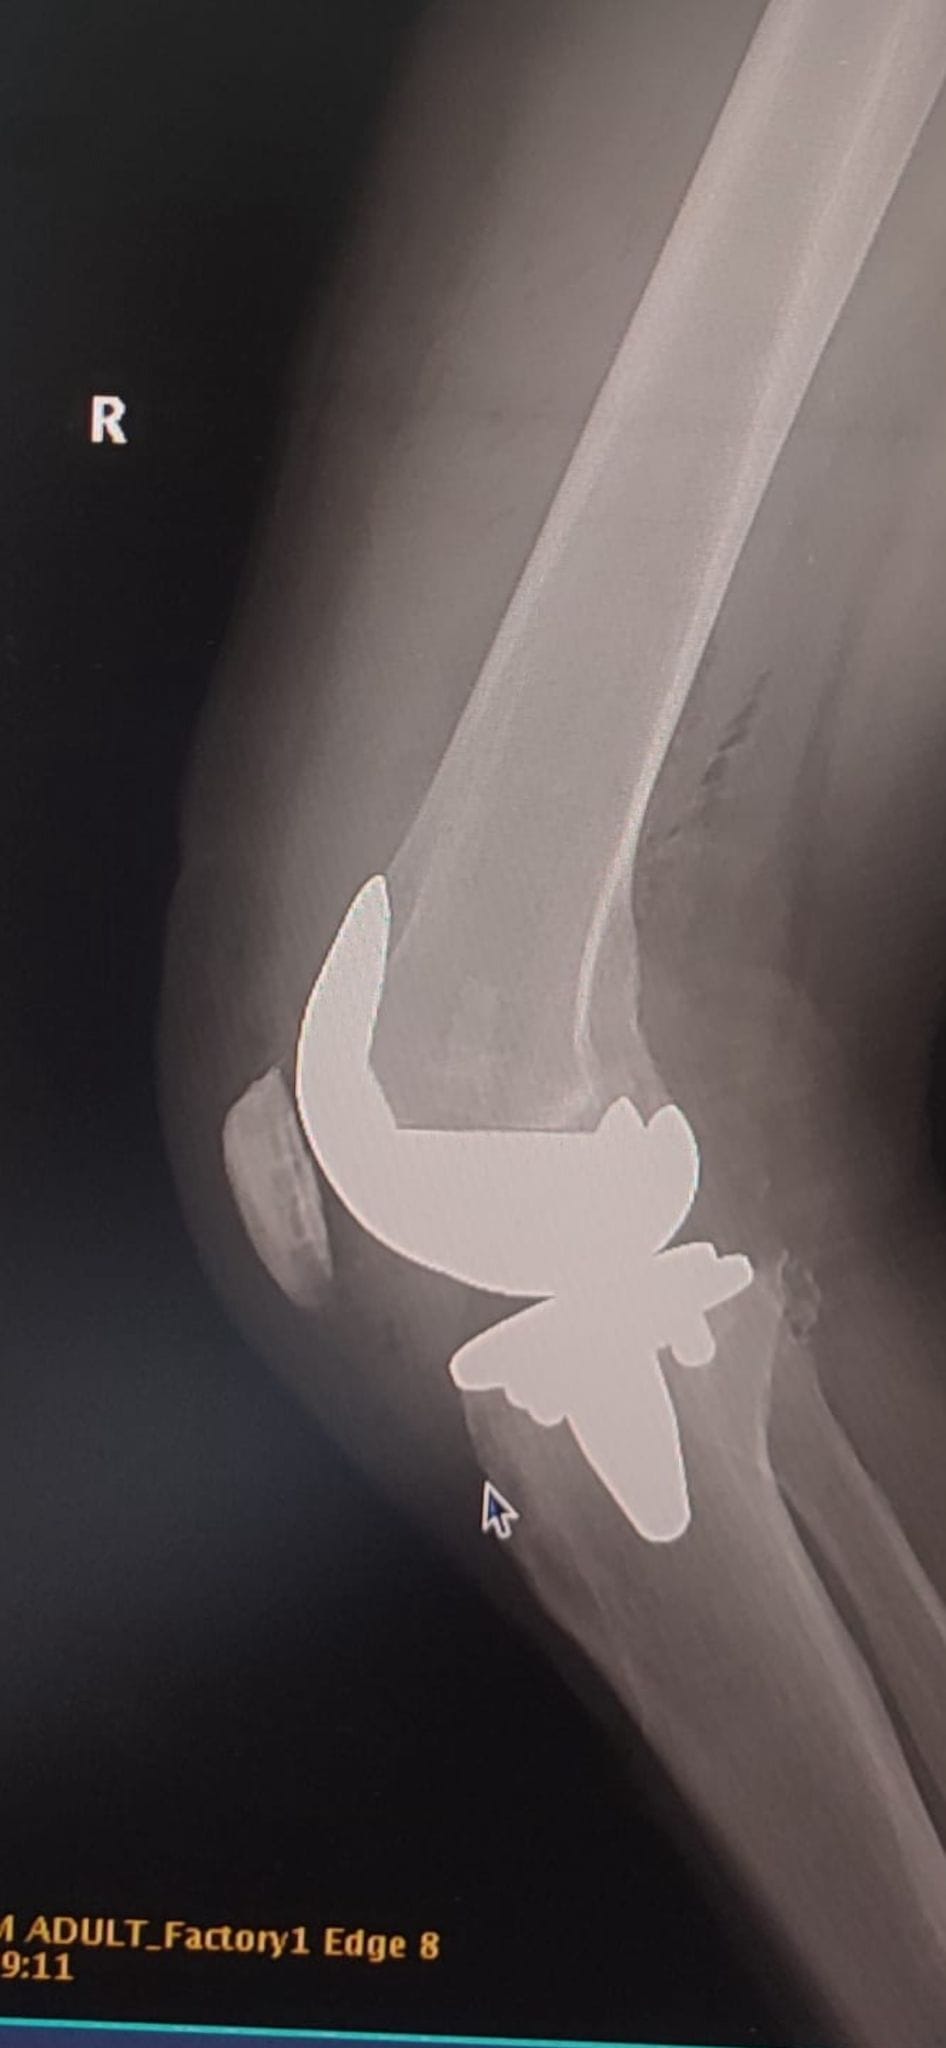

În cadrul clinicii Nova Vita, echipa medicală condusă de domnul Dr. Torok Barna, medic primar ortoped traumatolog,a realizat în cursul săptămânii trecute două artroplastii totale de genunchi cu endoproteză necimentată ATTUNE®, în premieră în sistemul medical din Tîrgu Mureș.

Attune ® Knee System Cementless este o proteză de ultimă generație, o inovație chirurgicală, dezvoltată special pentru nevoile pacienților care suferă de gonartroză (artroza genunchiului), oferindu-le o mobilitate de amplitudine mai mare și naturală.

Odată cu realizarea acestor intervenţii, Centrul Medical Nova Vita devine primul centru medical din Tîrgu Mureș și al doilea din țară care utilizează acest sistem de protezare de ultimă generație, recunoscut pe plan mondial – Attune ® Knee System Cementless, dl dr. Torok Barna fiind primul medic ortoped din Tîrgu Mureș care efectuează asemenea intervenții cu endoproteză necimentată și printre primii din România.